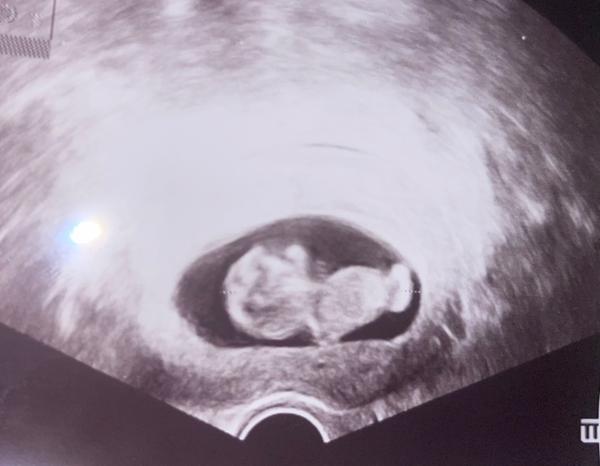

Bude to chlapček alebo dievčatko?

Vidite nieco na utz ze co by to mohlo byt?😅a nezda sa vam ze nostek je nejaky moc velky?😃co som kukala ine utz som take nevidela tsl nevkem ci je to normalne 😃

Ten nostek myslis tu sanku? Lebo ja tam ziadny nostek nevidim 🤷♀️ A nie nevidim co to bude, v tomto stadiu tehotenstva ti este ani skuseny gynekolog nepovie

Je to dievčatko. Ma veľkú hlavu, bude to žena 😉

Ja úprimne neviem ani rozoznať na 100% kde je hlava 😅 lekár ti povie najlepšie čo to bude